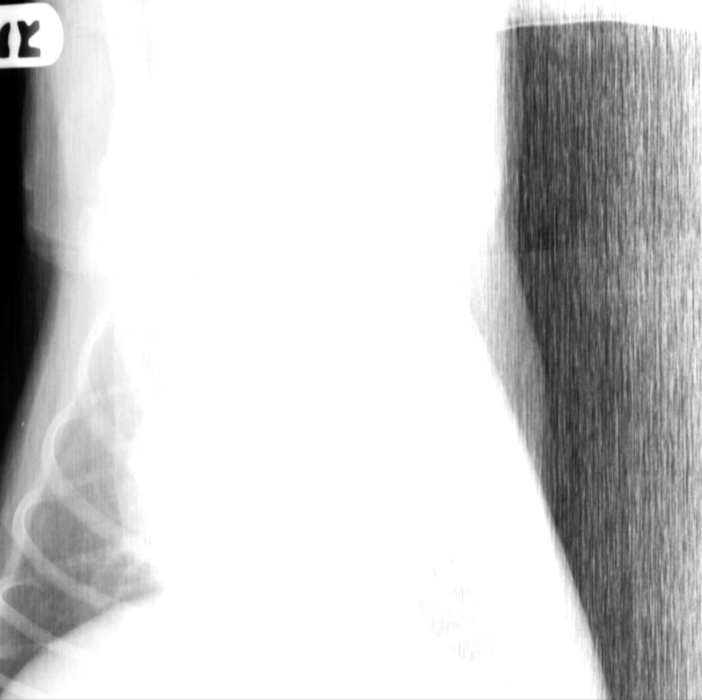

What is the problem with this film?

Not centered and incorrect film focal distance